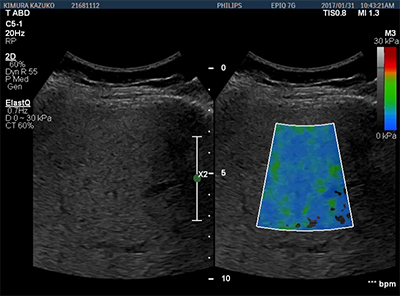

肝臓の組織弾性をシアウェーブにより非侵襲的に評価する新機能『ElastQ』をご紹介いたします。広範囲に設定できる関心領域の組織の硬さを,二次元のカラーマップで表現することができます。また,検査後でも保存したデータから任意のフレームにおいて複数回の測定による数値化が可能です。シアウェーブを,より臨床の場でご使用頂くための操作性を実現した機能となっております。

超音波診断装置EPIQ